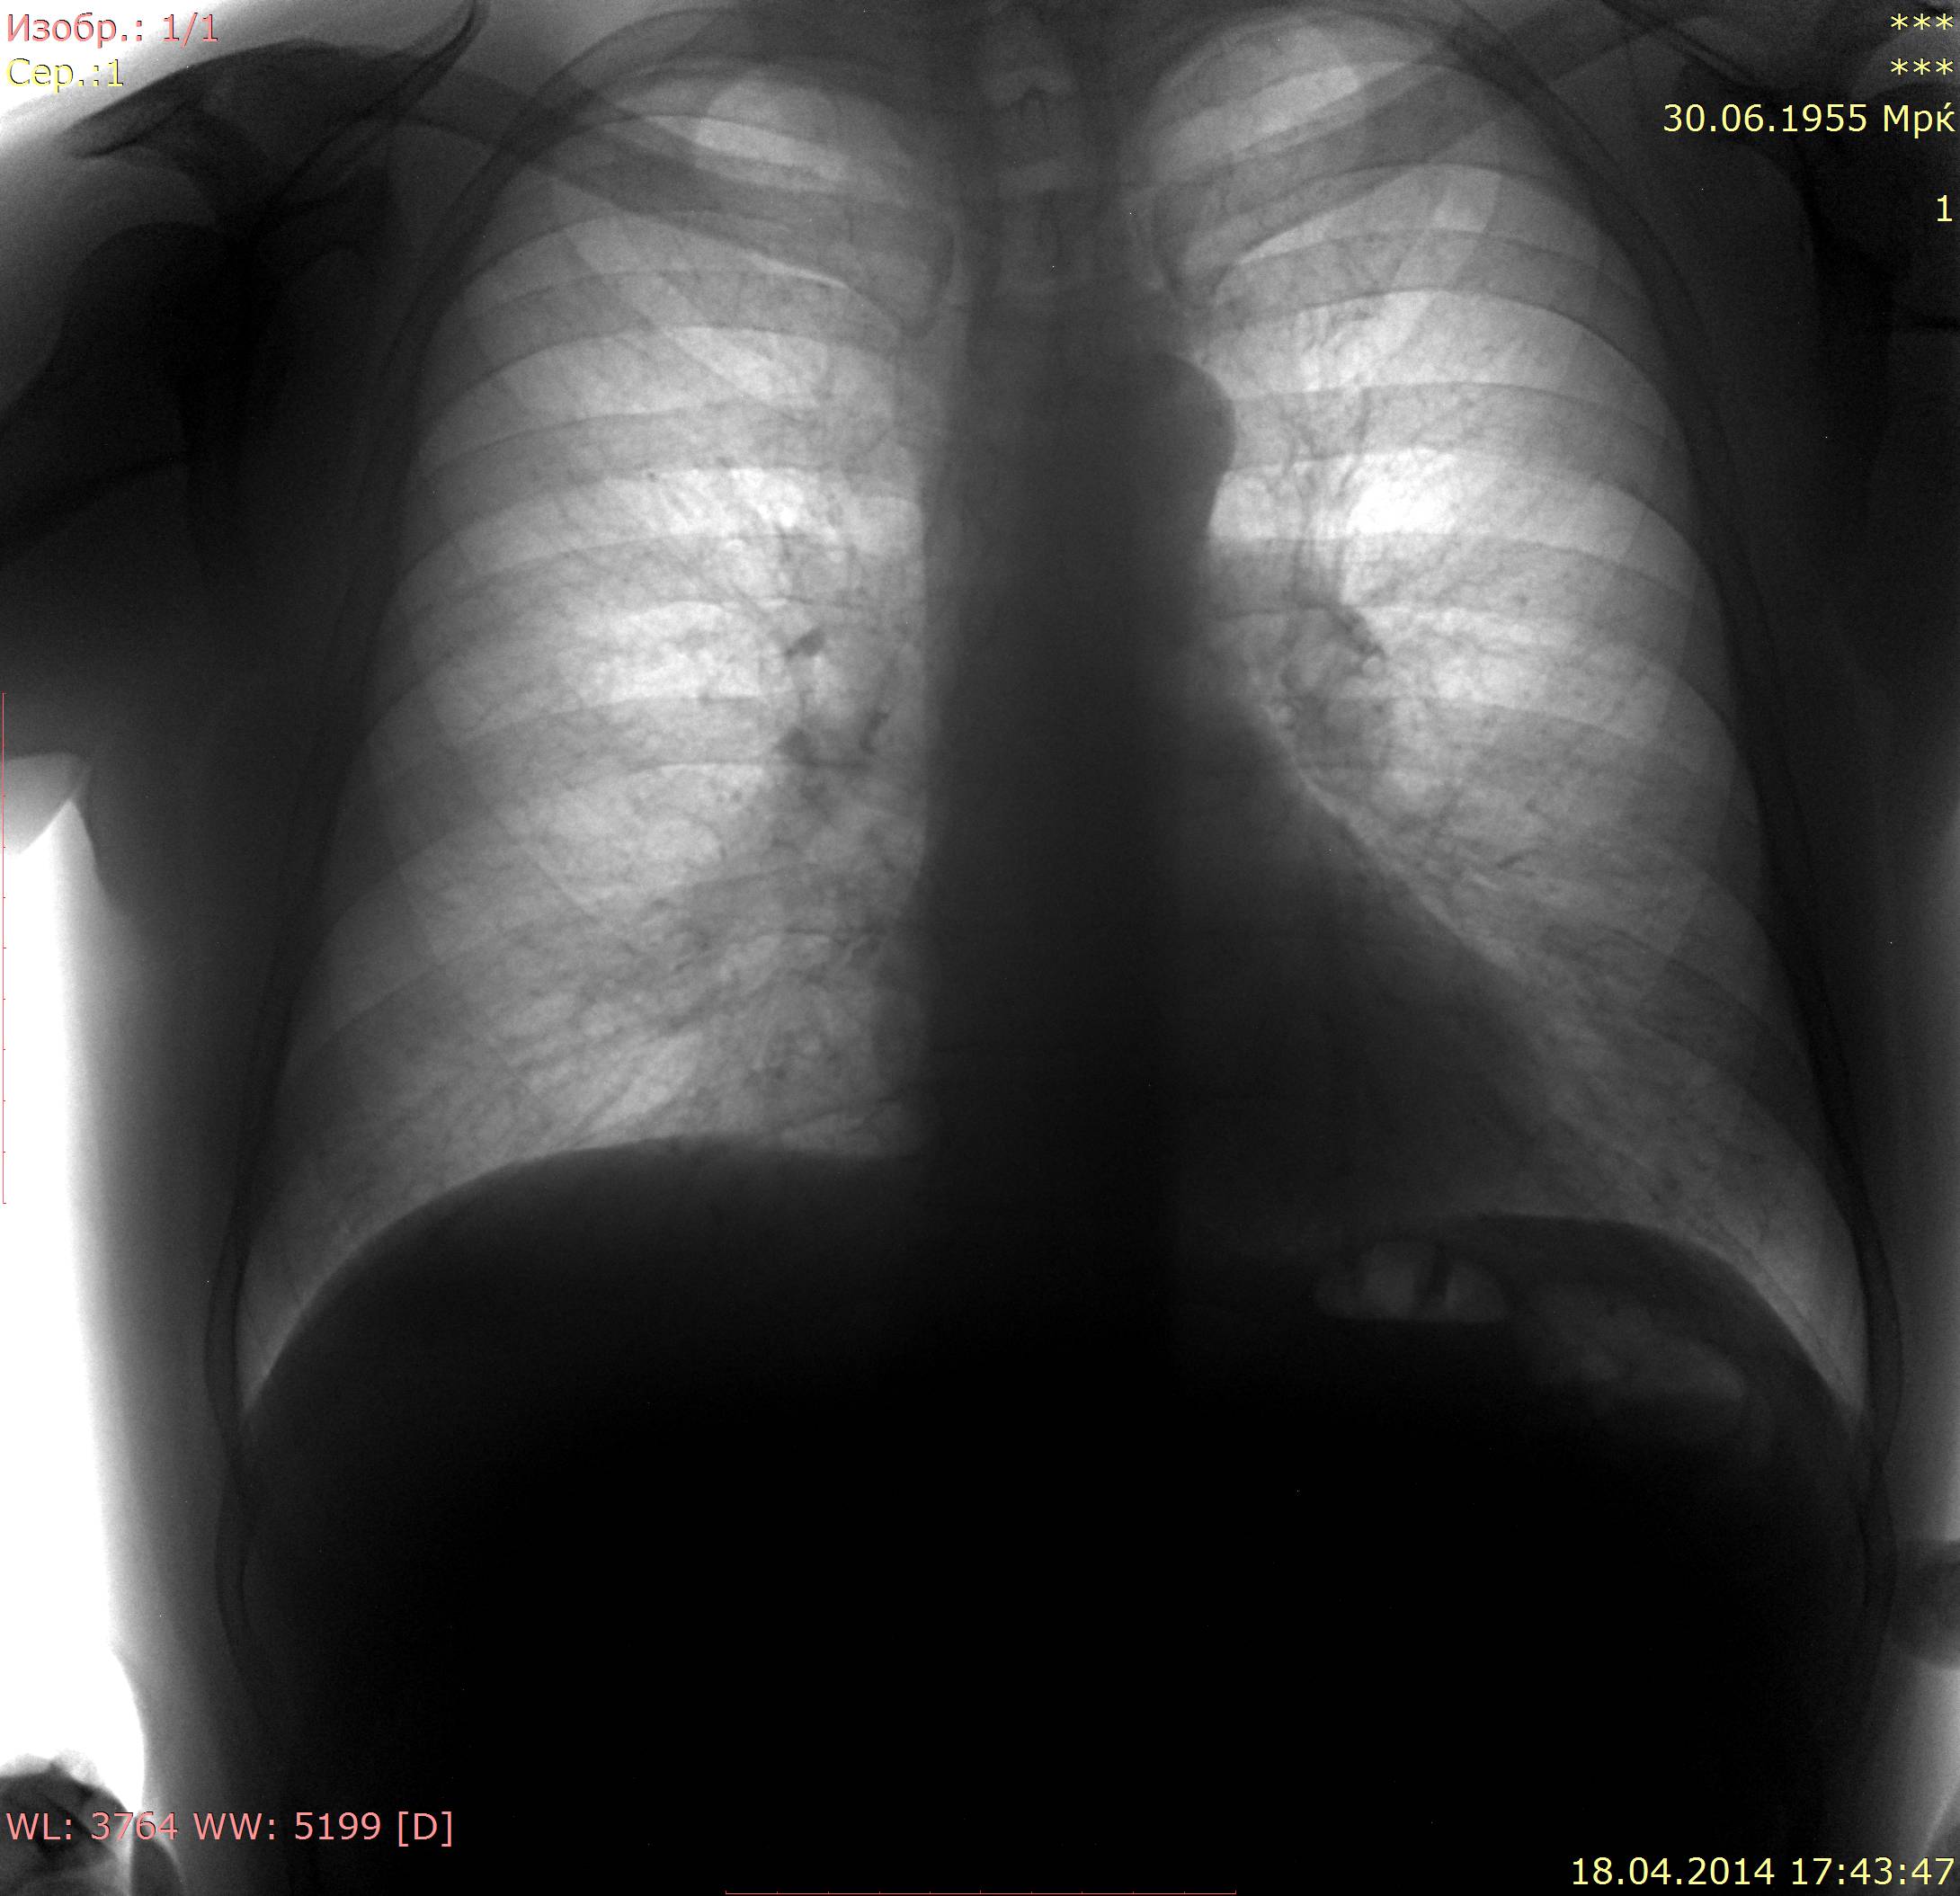

Пациент 1955 г.р, отмечал кашель, повышение температуры.

Контроль через 10 дней после лечения, состояние удовлетворительное.

Архивных снимков нет, есть описание 2 летней давности: усиление в рисунка в н\о легочных полей. В язычковых сегментах пневмония или что?

А я что-то по первому случаю динамики не вижу и на боковом как-то на пневмонию не похоже. Может это локальный пневмосклероз? В настоящее время жалоб особых нет.

По первому случаю : слева - ничего особенного. Можно пригласить на контроль через месяц и успокоиться. Но мозолит глаза кольцевидная тень справа. Что-то никто на неё внимания не обратил... А мне кажется - не скиалогия, а патология

Спасибо, можно уточнить, что значит "ничего особенного" : положительная динамика пневмонии (а по моему никакой динамики нет) или склероз/фиброз? А кольцевидной тени 10 дней назад не было, не могла же она за такие сроки образоваться, по-моему это сосуды.

"Ничего особенного" = склероз, фиброз, т.е. остатки пневмонии. Считаю динамику положительной.Назначьте контроль через месяц (после пневмонии - полагается). Тогда и разберётесь со всеми "тараканами". По кольцевидной тени Вам решать. Мне она, почему-то, бросилась в глаза. И на первом снимке , кажется, в этом месте не чисто. Может ещё кто-нибудь выскажется. Может, сильно бдительная я стала...

По-моему, первый (18.04) и последний (12.05) прямой снимок в схожих установках, а промежуточный (28.04) - с разворотом. Мне кажется, что динамика положительная, левый контур сердца стал более четким.

Хорошо. Шляпа, не удалось Вас сбить мне с верного пути.) Всё верно, динамика имеет место быть. Положительная, как ни крути!) Сердечный контур чётче - это раз, рисунок лёгочный не такой сближенный/сгущённый/обогащённый в язычках - два. Да и не только в язычках - в прикорневых зонах тоже тишина - уже и три, ага.) Ну, и размер плеврального пятна чуть меньше сбоку - ушла инфильтрация, остались только спайки - четыре! Все дела.) Осталось Вас спросить - Вы пневмонию заключали для получения контроля или просто ждали, как ждут, чтоб вздуть друг дружку Труляля и Траляля?))